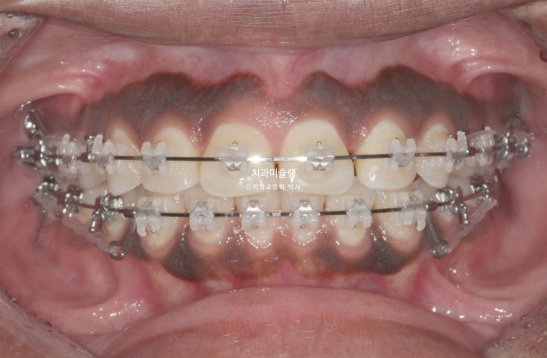

The patient opted for treatment using Clippy-C bracket orthodontics.

The treatment plan involves first closing the extraction spaces by retracting the protruded anterior teeth, followed by sequential intrusion of the supra-erupted molar.

This is the patient’s condition at 1 year and 2 months after the start of treatment.

Approximately one-third of the extraction space remains.